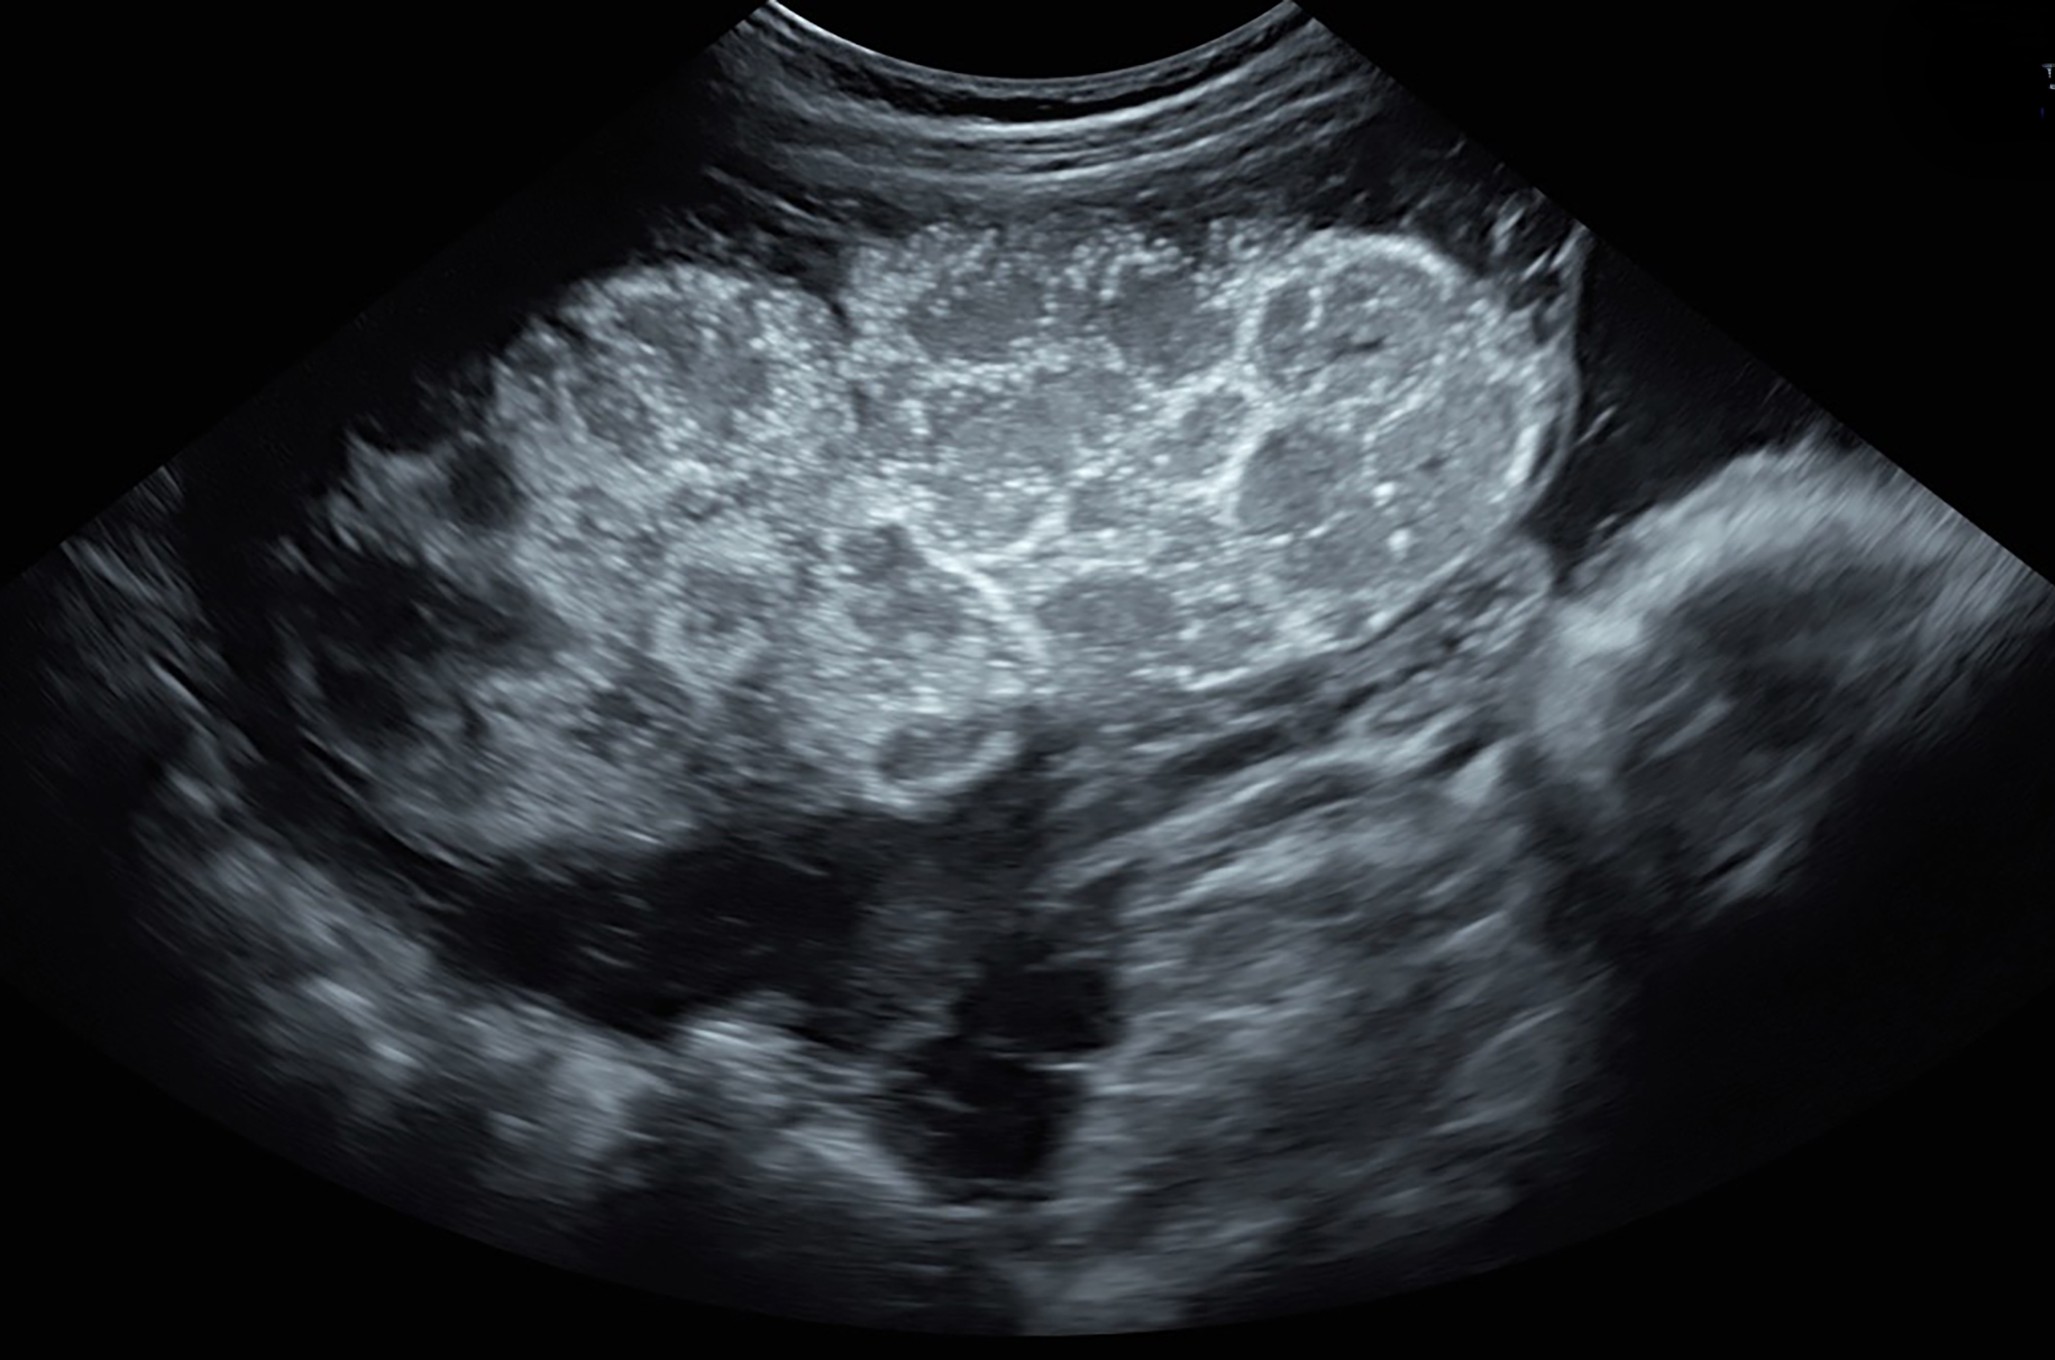

Placental mesenchymal dysplasia

Placental mesenchymal dysplasia (PMD) was first described by Moscoso et al. in 1991.167 It is an uncommon placental vascular abnormality characterized by mesenchymal stem villous hyperplasia, edema and cystic dilation.9,105,168 PMD complicates approximately 1 in 500 pregnancies (0.2%) and is often associated with placental mosaicism.9 There is a 3.6 : 1 female: male preponderance. Maternal serum alpha-fetoprotein (AFP) levels may also be markedly elevated in these pregnancies.169 Despite its clinical significance, PMD is underreported, and many sonographers, obstetricians and pathologists are unfamiliar with the condition, often confusing it with a hydatidiform mole.106,153,170,171,172

PMD is strongly associated with adverse pregnancy outcomes, including pre-eclampsia, FGR and fetal demise.106,173 It has also been found in association with Beckwith–Wiedemann syndrome and various congenital anomalies, including skeletal dysplasias and CHARGE syndrome.106,174,175,176 A systematic review by Nayeri et al. reported that only 9% of pregnancies with PMD resulted in a normal outcome for the baby106.

On ultrasound, PMD appears as a thickened placenta with multiple small cysts of varying size, creating a 'snowstorm' appearance that closely resembles a hydatidiform molar pregnancy (Figure 14; Video 8).9,105,106,169,172 Differentiating PMD from a molar pregnancy can be challenging, particularly in twin pregnancies in which a normal twin coexists with a cotwin that has an enlarged, cystic placenta.169 In complete molar pregnancy, the uterus is entirely filled with cystic tissue, showing a snowstorm appearance without identifiable fetal structures. Partial molar pregnancies, on the other hand, typically feature an enlarged cystic placenta coexisting with an abnormal fetus.105

14

(a–e) Grayscale ultrasound of placental mesenchymal dysplasia showing thickened placentas with multiple round cysts of varying size.